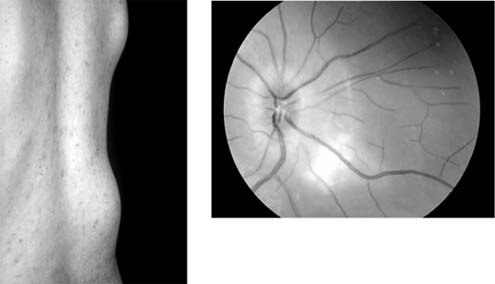

SARCOIDOSIS (new window  Figures 15-25 and new window  15-26)

Sarcoidosis is a multisystem disease with pulmonary, ocular (uveitis), cutaneous, and reticuloendothelial system manifestations. A granulomatous uveitis may be accompanied by cells in the vitreous periphlebitis, disk swelling, retinal neovascularization, and choroidal disease. New vessels may require photocoagulation. The systemic disease is controlled by the administration of oral corticosteroids and occasionally immunosuppressants. Infiltrative optic neuropathy is a rare cause of progressive severe visual loss.

Figure 15-25

Figure 15-25: Sarcoidosis. Focal periphlebitis and disk leakage may respond dramatically to systemic corticosteroids. Left: Before treatment. Right: After 6 weeks of treatment with prednisolone, 30 mg daily.

Figure 15-26

Figure 15-26: Sarcoidosis. Retinal pigment epithelial and choroidal disease may be very distinctive (left) and highlighted by fluorescein angiography (right).